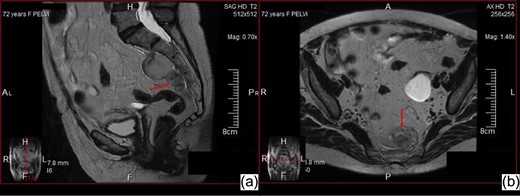

An asymptomatic 72-year-old woman with a history of hysterectomy without ovariectomy underwent a pelvic ultra-sound that revealed a cystic formation on the left ovary. Pelvic magnetic resonance (MR) confirmed the diagnosis of a left ovarian cyst and revealed a solid expansive mass in the presacral area that was ~6 cm in diameter, had a lobulated morphology, was strictly adherent to the sacral periosteum, was mainly adipose but exhibited an extremely non-homogeneous signal intensity (Fig. 1). The MR framework did not exclude the diagnosis of a malignant neoplasm such as a liposarcoma. The patient also underwent a contrast-enhanced CT scan that revealed the presence of an elongated formation of mainly adipose density (but with multiple areas of structural non-homogeneity) that was adherent to the presacral fascia (without bone infiltration) and exhibited a modest enhancement; the presence of multiple areas of structural non-homogeneity and modest enhancement precluded the exclusion of a malignant liposarcoma (Fig. 2). The risk that it was a malignant neoplasm contraindicated the execution of a CT-guided biopsy.

Abdominal MR sagittal (a) and axial (b) images—Solid expansive mass in the presacral area, with lobulated morphology, strictly adherent to the sacral periosteum, with adipose but non-homogeneous signal intensity.